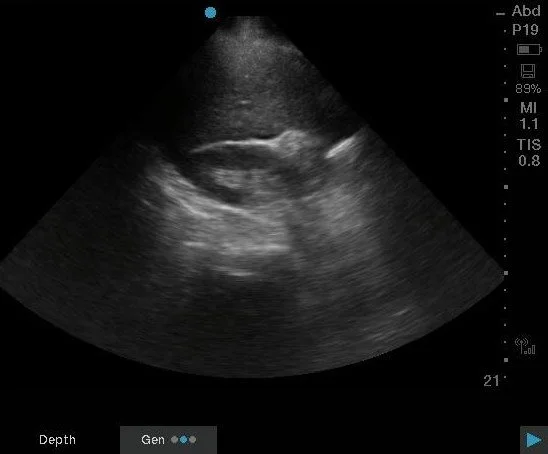

Dr. Aiad promptly took the ultrasound over to the patient and did a FAST and saved images that showed this:

Right upper quadrant free fluid, subtle.

This still image shows a sliver of free fluid within the hepatorenal space and potentially some free fluid near the liver edge. Dr. Aiad had the answer quickly: concern for a ruptured ectopic pregnancy.